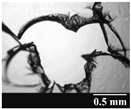

| Capsule Type | Time | RSC (%) | Area of Capsule Puncture (mm2) |

|---|---|---|---|

| GEL | Before storage | 15.26 ± 0.18 | 0.60 ± 0.16 |

| 1 month | 10.31 ± 0.21 | 0.74 ± 0.11 | |

| 3 months | 7.23 ± 0.28 | 1.01 ± 0.28 | |

| 6 months | 6.68 ± 0.12 | 1.14 ± 0.38 | |

| GEL-PEG | Before storage | 11.87 ± 0.09 | 0.54 ± 0.10 |

| 1 month | 10.68 ± 0.32 | 0.84 ± 0.12 | |

| 3 months | 8.74 ± 0.15 | 0.89 ± 0.14 | |

| 6 months | 7.12 ± 0.12 | 0.92 ± 0.07 | |

| HPMC | Before storage | 5.98 ± 0.11 | 0.79 ± 0.05 |

| 1 month | 5.45 ± 0.09 | 0.79 ± 0.04 | |

| 3 months | 4.84 ± 0.13 | 0.86 ± 0.08 | |

| 6 months | 4.62 ± 0.02 | 0.88 ± 0.03 |